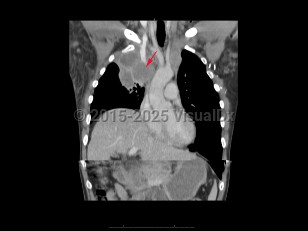

Superior vena cava syndrome (SVCS) results from obstruction of the superior vena cava (SVC), inhibiting venous return from the head, neck, and upper extremities. The most common causes are compression of the SVC due to mediastinal malignancy, followed by thrombosis of the SVC secondary to an indwelling catheter or pacemaker wires. Common symptoms are facial and arm edema, distended neck and chest veins, facial plethora, dyspnea, and cough.

Obstruction of the SVC can cause cervical venous pressures to increase 5-10 times normal. Symptoms usually appear over a period of weeks, and there may be mild improvement as collateral circulation develops. Malignancy is the most common cause, with non-small cell lung cancer and small cell lung cancer making up the majority of cases, followed by lymphoma, metastasis, germ cell cancer, thymoma, and mesothelioma. Thrombosis of the SVC has become more common as the use of indwelling catheters has increased and now contributes to 40% of SVCS cases. Rare causes include benign tumors, aortic aneurysm, thyromegaly, fibrosing mediastinitis from prior irradiation, histoplasmosis, or Behçet's syndrome.

Severity of symptoms depends on the degree of obstruction of the SVC. Facial edema, especially around the eyes; distended neck veins; dyspnea; and cough are common. Signs of cerebral and/or laryngeal edema and cardiorespiratory symptoms are associated with more severe disease and require urgent evaluation. This includes stridor, syncope, headache, vision changes, dizziness, confusion, and obtundation. Esophageal varices are a rare complication, and severity depends on whether the obstruction is proximal or distal to the azygous vein.